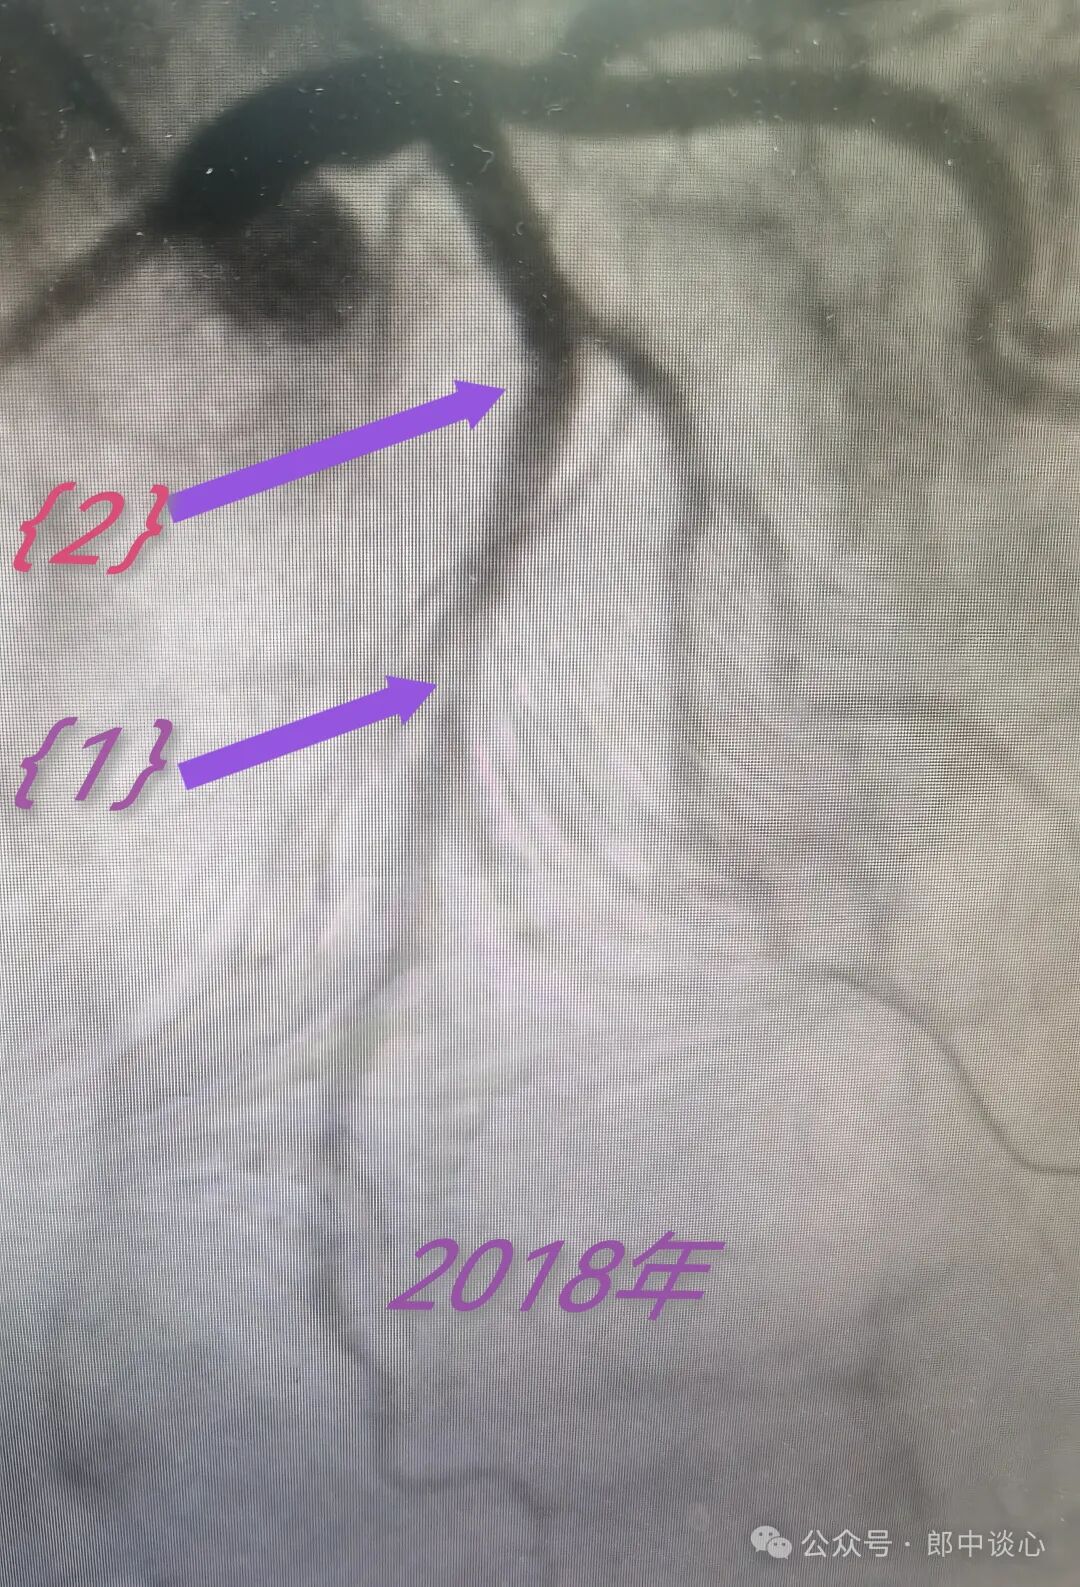

6年前,也就是2018年,他心绞痛入院。

粗大的对角支有个严重的狭窄(小箭头所示),前降支主支有个临界病变{1},而{2}部位造影上当时看着很正常。

考虑对角支是缺血血管,做了PTCA,即刻效果也不错,术后心绞痛也缓解了。